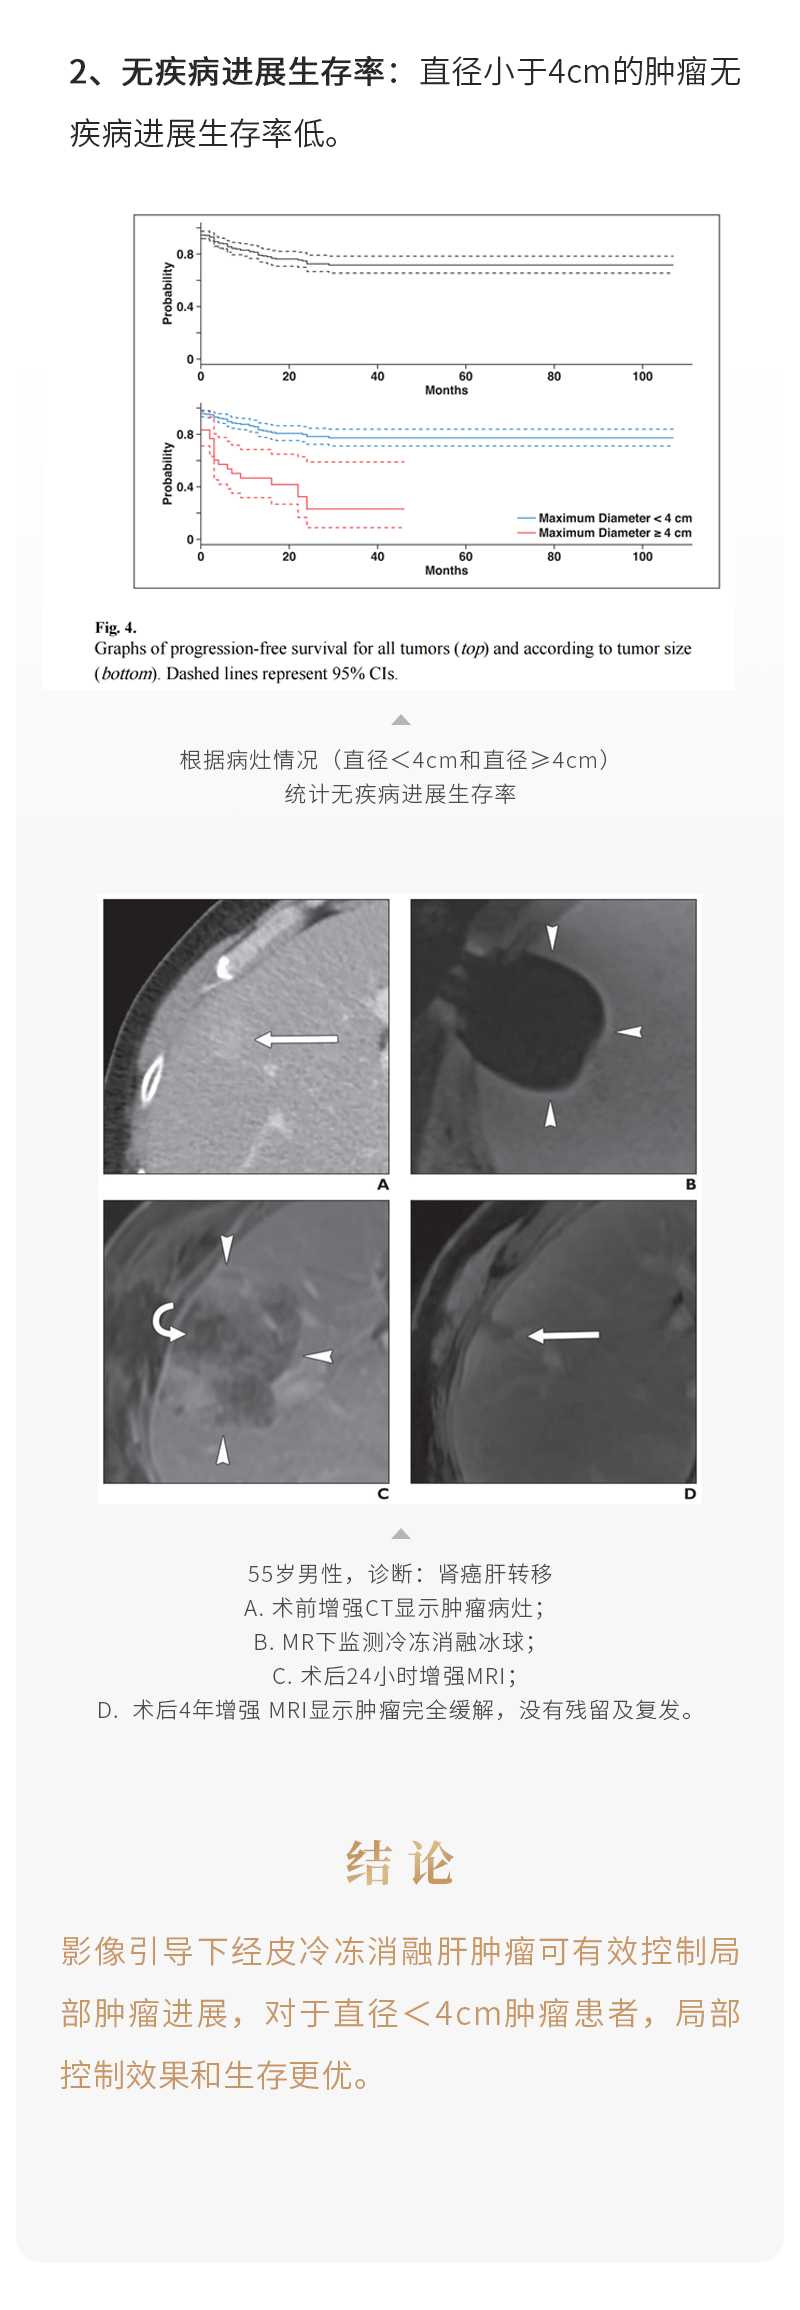

冷冻消融治疗肝转移瘤安全有效——【海杰亚科研资讯】第236期